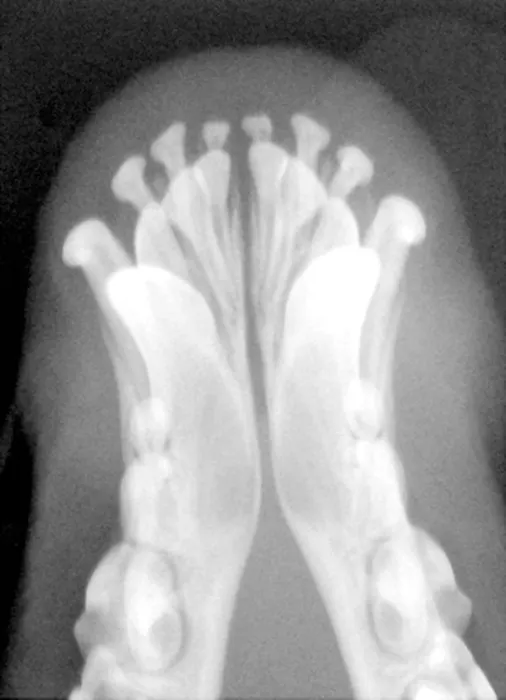

Persistent Deciduous Canine Teeth in a Dog

Presence of these teeth during eruption of permanent canines can cause the maxillary canine to be pushed mesially and the mandibular canine to be pushed lingually, resulting in malocclusion.